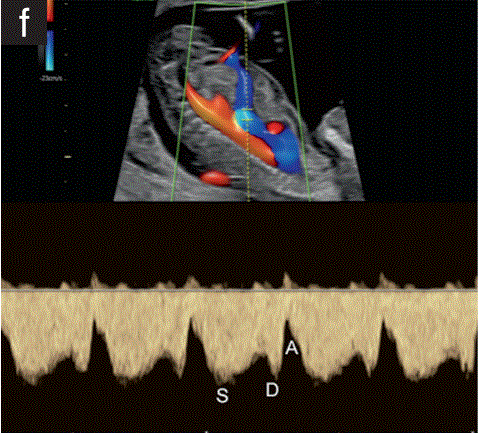

静脉导管通常在偏右侧切面上进行评估。彩色多普勒用于识别通过脐静脉和静脉导管返回到右心房的血流。一个1mm的脉冲波多普勒门可以用来显示波形,它具有一个典型的外观(图1f)。PIV是通过自动跟踪来测量的。

胎儿mt是什么检查什么疼吗【文献学习/规范指南】ISUOG实践指南(2023更新): 11-14周胎儿超声检查(全文)_https://www.jmylbn.com_新闻资讯_第31张

图1 11+0至14+0周胎儿超声检查可获得的测量值。

(f)胎儿胸部和腹部的旁矢状面图,彩色和脉冲多普勒,显示脐静脉和静脉导管(DV)的血流。在正常情况下,DV速度波形是三相的,在收缩期(S)、舒张期和舒张期末(a波)有顺行流动。